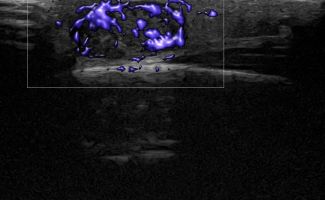

Η τεχνική του Έγχρωμου Doppler μελετάει την αγγείωση της βλάβης. Η τεχνική του Παλμικού Doppler μελετάει την παρουσία αρτηριακών ή φλεβικών στοιχείων εντός της βλάβης. Επίσης πολύ χρήσιμη είναι η Ελαστογραφική Μελέτη η οποία μελετάει τη σκληρότητας της βλάβης. Οι τεχνικές αυτές μας βοηθούν να χαρακτηρίσουμε αν η βλάβη είναι αγγειακού τύπου και αν έχει καλοήθη η ύποπτα χαρακτηριστικά.

Η εξέταση δεν απαιτεί κάποια ιδιαίτερη προετοιμασία. Ο εξεταζόμενος, ανάλογα με την περιοχή του ευρήματος, εξετάζεται ξαπλωμένος ή καθιστός μετά από την τοποθέτηση ζελέ στην περιοχή. Με τη χρήση ειδικών ηχοβόλων κεφάλων υψηλής ευκρίνειας γίνεται η εξέταση. Εκτός από την ασπρόμαυρη εξέταση (B- mode) γίνεται μελέτη με έγχρωμο Power Doppler και Ελαστογραφία. Η διάρκεια της εξέτασης είναι 20-30 λεπτά.